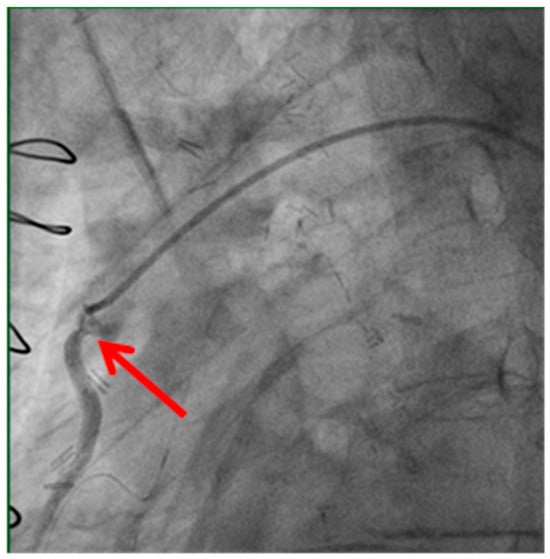

Technical issues remain a principal cause of PMI, with early graft thrombosis or occlusion being leading indications for uCAG (Figure 1, Figure 2, Figure 3 and Figure 4 illustrate typical technical causes, including proximal anastomotic stenosis, kinking, distal anastomotic stenosis, and misplaced anastomoses). Notable contributors include anastomotic stenosis, kinking, overstretching of grafts, and temporary graft spasm [,]. Prueßer et al. demonstrated that 30% of PMI cases detected via CAG were graft-related failures []. In this context, uCAG often reveals technical failures immediately post-surgery, providing the advantage of guiding targeted percutaneous coronary intervention or revascularization. Graft spasm, which can be relieved by nitrates, may also lead to acute ischemia. It refers to the temporary constriction of the bypass graft, reducing blood flow to the myocardium. This condition can be caused by various factors, including surgical trauma, inflammation, or the release of vasoactive substances [].

Figure 1.

Stenosis of proximal anastomosis.

Stenosis of the proximal anastomosis (shown by the red arrow) visualized on early postoperative coronary angiography. This image demonstrates a technical cause of early graft failure, which can lead to perioperative myocardial infarction if not promptly identified and treated.